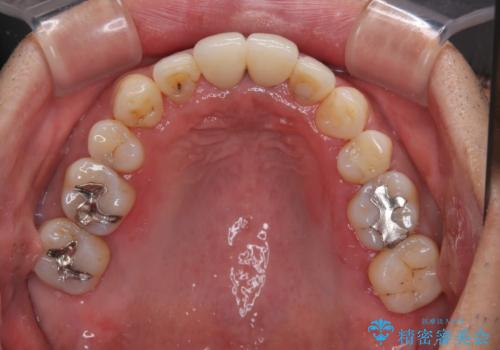

八重歯と突出感を改善 ワイヤー装置での矯正治療

- 八重歯を気にして来院された患者様です。

上顎前歯の突出感と右上の八重歯を気にされていたので、上顎左右の第一小臼歯2本を抜歯し、ワイヤー装置にて矯正治療を行うこととしました。

上顎前歯に装着されていた保険診療の前歯は見た目が気になるとのことであったので、矯正治療後にオールセラミッククラウンにて補綴治療を行うこととしました。

食いしばりにより奥歯がすり減っており、咬み合わせが定まるまで時間がかかりましたが、整った口もに仕上がりました。